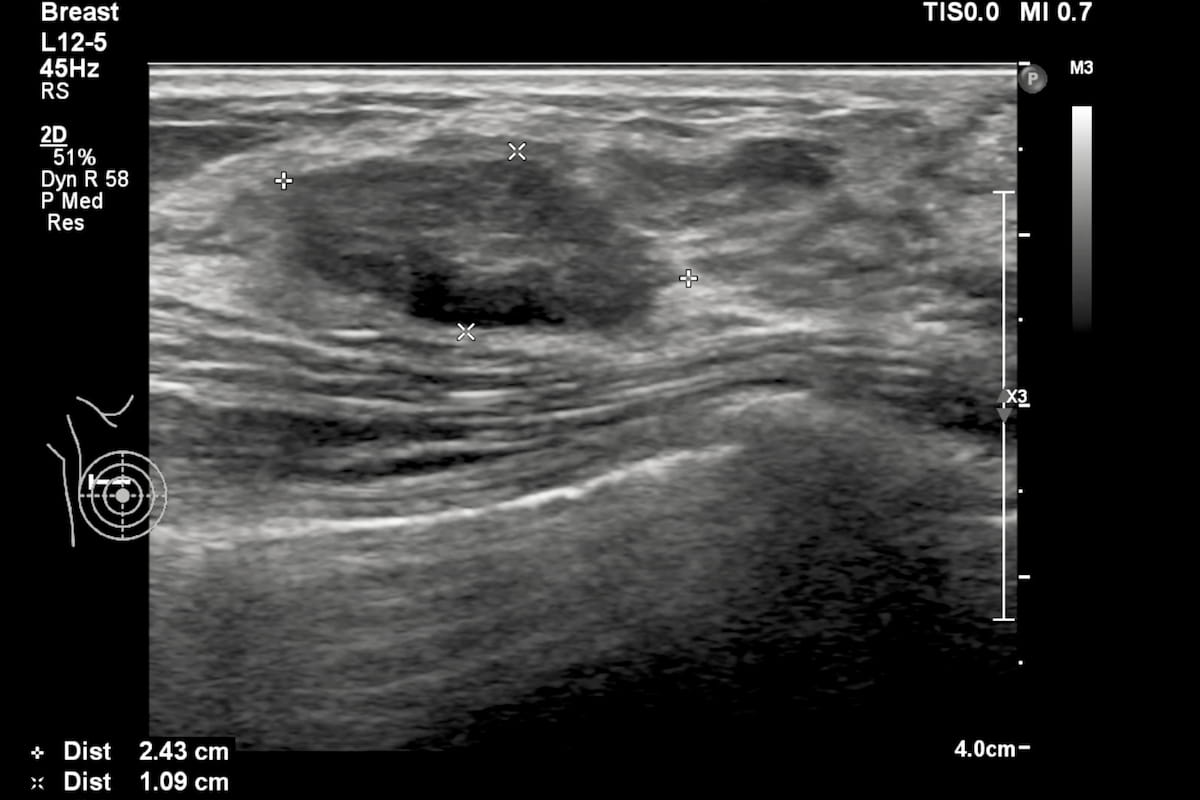

In order to facilitate optimal detection and assessment of liver fibrosis and steatosis, the newly launched Hepatus 6 Diagnostic Ultrasound System offers the capabilities of real-time two-dimensional ultrasound with visual transient elastography in one device.